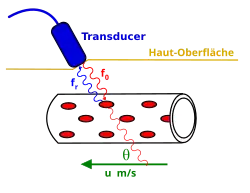

Efeito Doppler em Imageamento por Ultrassom

Quando a fonte de um ultrassom está se movendo, a frequência da onda observada por um receptor estacionário é diferente da frequência da fonte. Esse fenômeno é chamado efeito Doppler. Quando a fonte está se movendo na direção do receptor, a frequência é maior, e quando a fonte se afasta do receptor, a frequência é menor.

Em aplicações médicas de ultrassom, a onda detectada é frequentemente uma reflexão de tecido em movimento, como hemácias no sangue. A diferença entre as frequências contém informações sobre a velocidade do objeto. Essas informações podem ser usadas para criar mapas de fluxo sanguíneo.

Na física clássica, em que as velocidades da fonte e do recetor em relação ao meio são inferiores à velocidade das ondas no meio, a relação entre a frequência observada e a frequência emitida é dada por:[17]

onde

- é a velocidade de propagação das ondas no meio;

- é a velocidade do receptor em relação ao meio. Na fórmula, é adicionado a se o recetor estiver a mover-se em direção à fonte, subtraído se o recetor estiver a afastar-se da fonte;

- é a velocidade da fonte em relação ao meio. é subtraído de se a fonte se estiver a mover em direção ao recetor, somado se a fonte se estiver a afastar do recetor.

Note-se que esta relação prevê que a frequência diminuirá se a fonte ou o recetor estiverem a afastar-se um do outro.